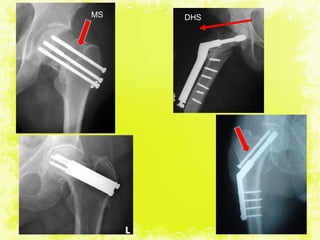

INTERNAL FIXATION for fracture neck

of femur

Choices of implants for internal fixation:

Multiple pins (Knowles,Moore): -

- impacted fractures

- medically unfit persons

- fractures in children.

ASNIS: - provide improved pullout and bending and

torque strengths.*

Fixed angle nail

Sliding or Telescopic nails (Dynamic Hip Screws):

nail offers collapsibility

continuous impaction at the fracture site

lessen the chances of nail penetration.

4/17/2014 30

DHSMS